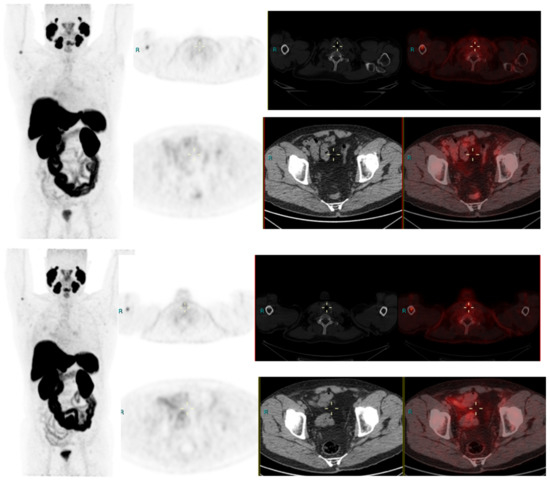

We conducted a separate subgroup analysis of 61 patients (Table 4) who had repeat imaging. Thirty had indeterminate findings on initial PSMA PET CT and the findings changed to a positive lesion in 14 (10 with known small indeterminate pelvic lymph node and four with known indeterminate prostate focus, PSA increase of 0.7 to 3.0 in 6 months), negative in eight (four with pelvic lymph node, four with uptake in bones on prior PET CT, PSA increase of 0.13–2). Six patient had the same indeterminate small pelvic lymph node, two had the same indeterminate retroperitoneal lymph node (PSA increase of 0.4 to 2.5). Overall, the follow-up PSMA PET CT was able to conclude in 24/30 patients on follow-up. Of the 31 patients who had repeat PSMA PET CT scans done for a further rise in PSA levels (PSA rise range 0.3–10), 24 had new lesions (prostate lesion in four, prostate and seminal vesicle involvement in four, pelvic/retroperitoneal lymph nodes in 12, new bone lesion in four) and eight had negative scans even on repeat imaging (PSA rise 0.3–2.3). For example, patient in Figure 2 had negative scan at PSA of 3.4 ng/mL, PSA velocity of 1.3 ng/mL in six months. The uptake in right humerus is at the site of known prior humerus fracture and therefore it was categorized as PSMA RADS 1 B (7). Another patient in Figure 3 had and indeterminate lymph node at PSA 6.5 ng/mL, after rise of 3 ng/mL in 2 years, it was categorized as RADS 3A(7). An interesting finding in this case was the consolidation changes in the right upper lobe, which resolved in a follow-up CT performed after 2 months (Figure 4).

Figure 2.

Radical prostatectomy—Negative scan at PSA 2.1 and 3.4 ng/mL, PSA rise of 1.3 ng/mL after 6 months. PSMA RADS 1 B, due to uptake in prior known humeral fracture.